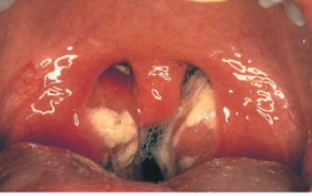

- Sore throat and tonsils.

- Swollen lymph glands (nodes) in the neck and, less commonly, the armpits and groin area. (kissing tonsils)